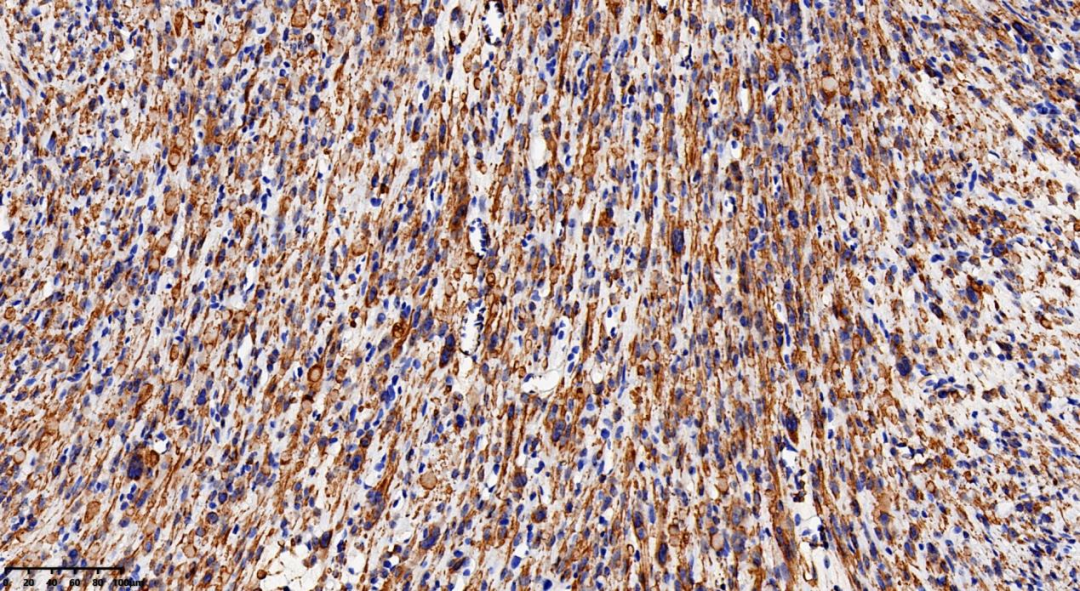

免疫组织化学染色:

FH

2307245-2号蜡块:FH(-), ATRX(+),ER(+), PR(+), Desmin(+), SMA(+), Caldesmon(+), CD10(-),P53(野生型表达), P16(斑片状), CD34(血管+),  ALK(-)。

免疫组化及分子检测:

由于上述组织学特征也可以在其他亚型的子宫平滑肌瘤中见到,因此不能单独作为确诊依据,须结合免疫组织化学和遗传学检测。

肿瘤特征性的表现为FH染色缺失、2SC弥漫性颗粒状着色、 以及1q43杂合性缺失。

FH表达缺失和2SC阳性有助于识别延胡索酸水合酶缺乏型平滑肌瘤。建议对所有形态学具有提示特征的子宫平滑肌瘤常规进行免疫组织化学筛查。